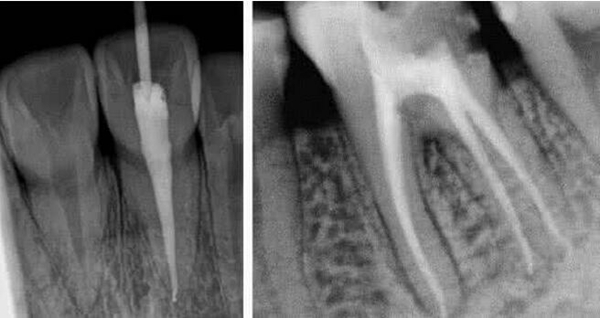

根管治疗是治愈牙髓炎和根尖炎的有效方式,麦芽口腔全科医师表示要尽量拯救和保存每一颗牙齿,而根管治疗就是目前保存患牙较好的治疗方法之一,也是残冠残根能选择的主要治疗方法。那么如何选择根管治疗的机构呢?

1、技术:麦芽微创微痛根管治疗

麦芽显微根管治疗与普通根管治疗相比: